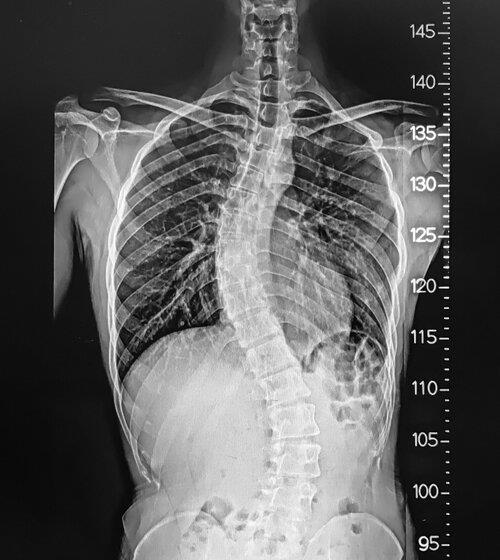

AFFECTING THE SPINE, INCLUDING THE BONES, NERVES, MUSCLES, AND OTHER STRUCTURES IN THE BACK AND NECK. THESE CONDITIONS MAY INCLUDE HERNIATED DISCS, SPINAL STENOSIS, SCOLIOSIS, DEGENERATIVE DISC DISEASE, AND INJURIES FROM ACCIDENTS OR OTHER TRAUMA. DR. ANDREW CHUNG USES VARIOUS TECHNIQUES, INCLUDING SURGERY AND MINIMALLY INVASIVE PROCEDURES, TO ALLEVIATE PAIN AND IMPROVE

A CERTIFIED DUAL FELLOWSHIP SPINE SURGEON IS ABLE TO DIAGNOSE THE CAUSE OF NECK PAIN IN SURPRISE AND RECOMMEND TREATMENT OPTIONS. DR. ANDREW CHUNG WILL FIRST EVALUATE THE PATIENT'S SYMPTOMS AND MEDICAL HISTORY AND THEN PERFORM A PHYSICAL EXAMINATION TO ASSESS THE PATIENT'S RANGE OF MOTION AND ANY AREAS OF TENDERNESS OR WEAKNESS. HE MAY ALSO ORDER IMAGING STUDIES, SUCH AS XRAYS OR MRIS, TO HELP THEM IDENTIFY THE UNDERLYING CAUSE OF THE NECK PAIN. IF YOU ARE SUFFERING FROM HEADACHES, STIFFNESS, AND DIFFICULTY MOVING THE HEAD, YOU CAN SCHEDULE YOUR APPOINTMENT WITH THE SURGEON AT BANNER HEALTH CLINIC. FOR MORE DETAILS, CLICK ON THE WEBSITE.

IN ARIZONA, BACK FUSION IS A COMPLEX AND DELICATE SURGERY THAT REQUIRES A HIGH LEVEL OF SKILL AND EXPERIENCE. DR. ANDREW CHUNG, WHO IS A CERTIFIED DUAL FELLOWSHIP SPINE SURGEON, HAS THE EXPERTISE AND NECESSARY KNOWLEDGE TO PERFORM THE PROCEDURE SAFELY AND EFFECTIVELY. WITH HIS PROFESSIONAL GUIDANCE, PATIENTS CAN EXPECT TO EXPERIENCE A SIGNIFICANT REDUCTION IN PAIN AND IMPROVEMENT IN THEIR SPINAL FUNCTION. THIS MICRO-INVASIVE PROCEDURE IS COMMONLY USED TO TREAT SPINE ISSUES SUCH AS DEGENERATIVE DISC DISEASE, SPINAL STENOSIS, AND SCOLIOSIS WITH BONE GRAFTS, METAL PLATES, AND SCREWS TO STABILIZE THE SPINE. FOR MORE DETAILS, CLICK ON THE WEBSITE.